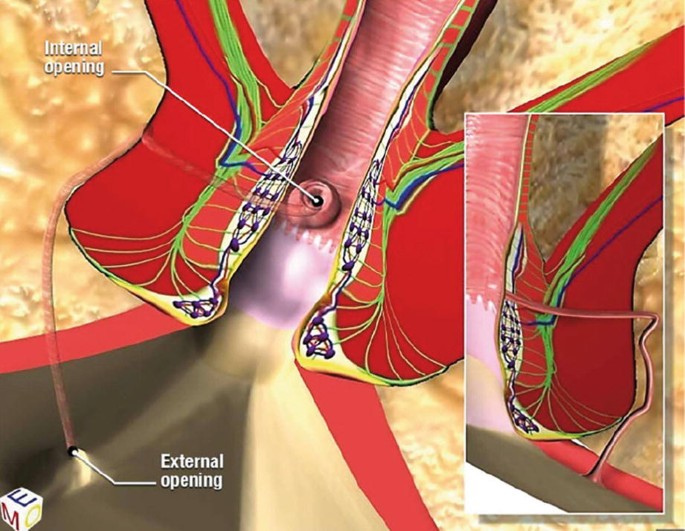

VAAFT (Video-Assisted Anal Fistula Treatment) is a modern, minimally invasive, sphincter-saving technique used to treat anal fistulas,

Read More

VAAFT (Video-Assisted Anal Fistula Treatment) is a modern, minimally invasive, sphincter-saving technique used to treat anal fistulas,

Read More